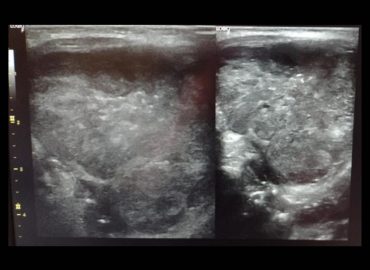

Antecedentes: – Sexo femenino – 50 años – MC: nódulo autopalpable en CSE MI. – Examen mamario: dos nódulos en […]